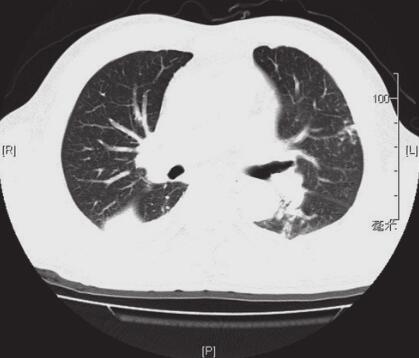

入院体格检查:T 36.8℃,P 86次/分,R 20次/分,BP 131/82mmHg,SpO2 91%,浅表淋巴结不大,颈静脉无充盈,双肺呼吸音粗,双下肺可闻及湿啰音。心率86次/分,律欠齐,未及明显杂音。腹平软,双下肢无水肿。入院后完善相关检查,胸部CT(图2)示:右肺中下叶及左舌段下叶见大片状模糊影,内部密度不均匀,见支气管充气征;两侧少量胸腔积液。血常规(3月3日):WBC 23.71×109/L,N% 88.8%。CRP 74.8mmol/L。血气分析(3月3日鼻导管吸氧3L/min):pH 7.41,PCO2 32.00mmHg;PO2 61.0mmHg;CRP 74.8mmol/L;BNP 58.0pg/ml。凝血功能,大、小便常规正常。血管炎4项、自身免疫抗体谱、结核抗体、支原体、衣原体抗体、HIV均为阴性。肿瘤全套:正常范围内。多次痰找抗酸杆菌、痰找癌细胞均为阴性。痰涂片:见G-杆菌;痰培养:肺炎克雷伯杆菌。血培养:阴性。仔细追问病史,患者诉在修车过程中有“吸入一大口汽油”史。

图2 2012年3月3日胸部CT

右肺中下叶及左舌段下叶见大片状模糊影,内部密度不均匀,见支气管充气征;两侧少量胸腔积液